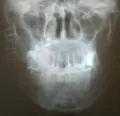

Первые дни только привыкал к шинам, но быстро адаптировался, так как не впервой. От госпитализации я отказался, решил, что в домашних условиях справлюсь. Сделал контрольный снимок, проконсультировался с хирургом-стоматологом и он, посмотрев на снимок и на шины, сказал, что процесс заживления идёт нормально.

Снимок прилагаю (был сделан на 5-й день после шинирования).

Теоретически все нормально, но справа имеется серьёзный костный дефект с повреждением нижнечелюстного канала. Рекомендую Вам обратиться к лечащему врачу.